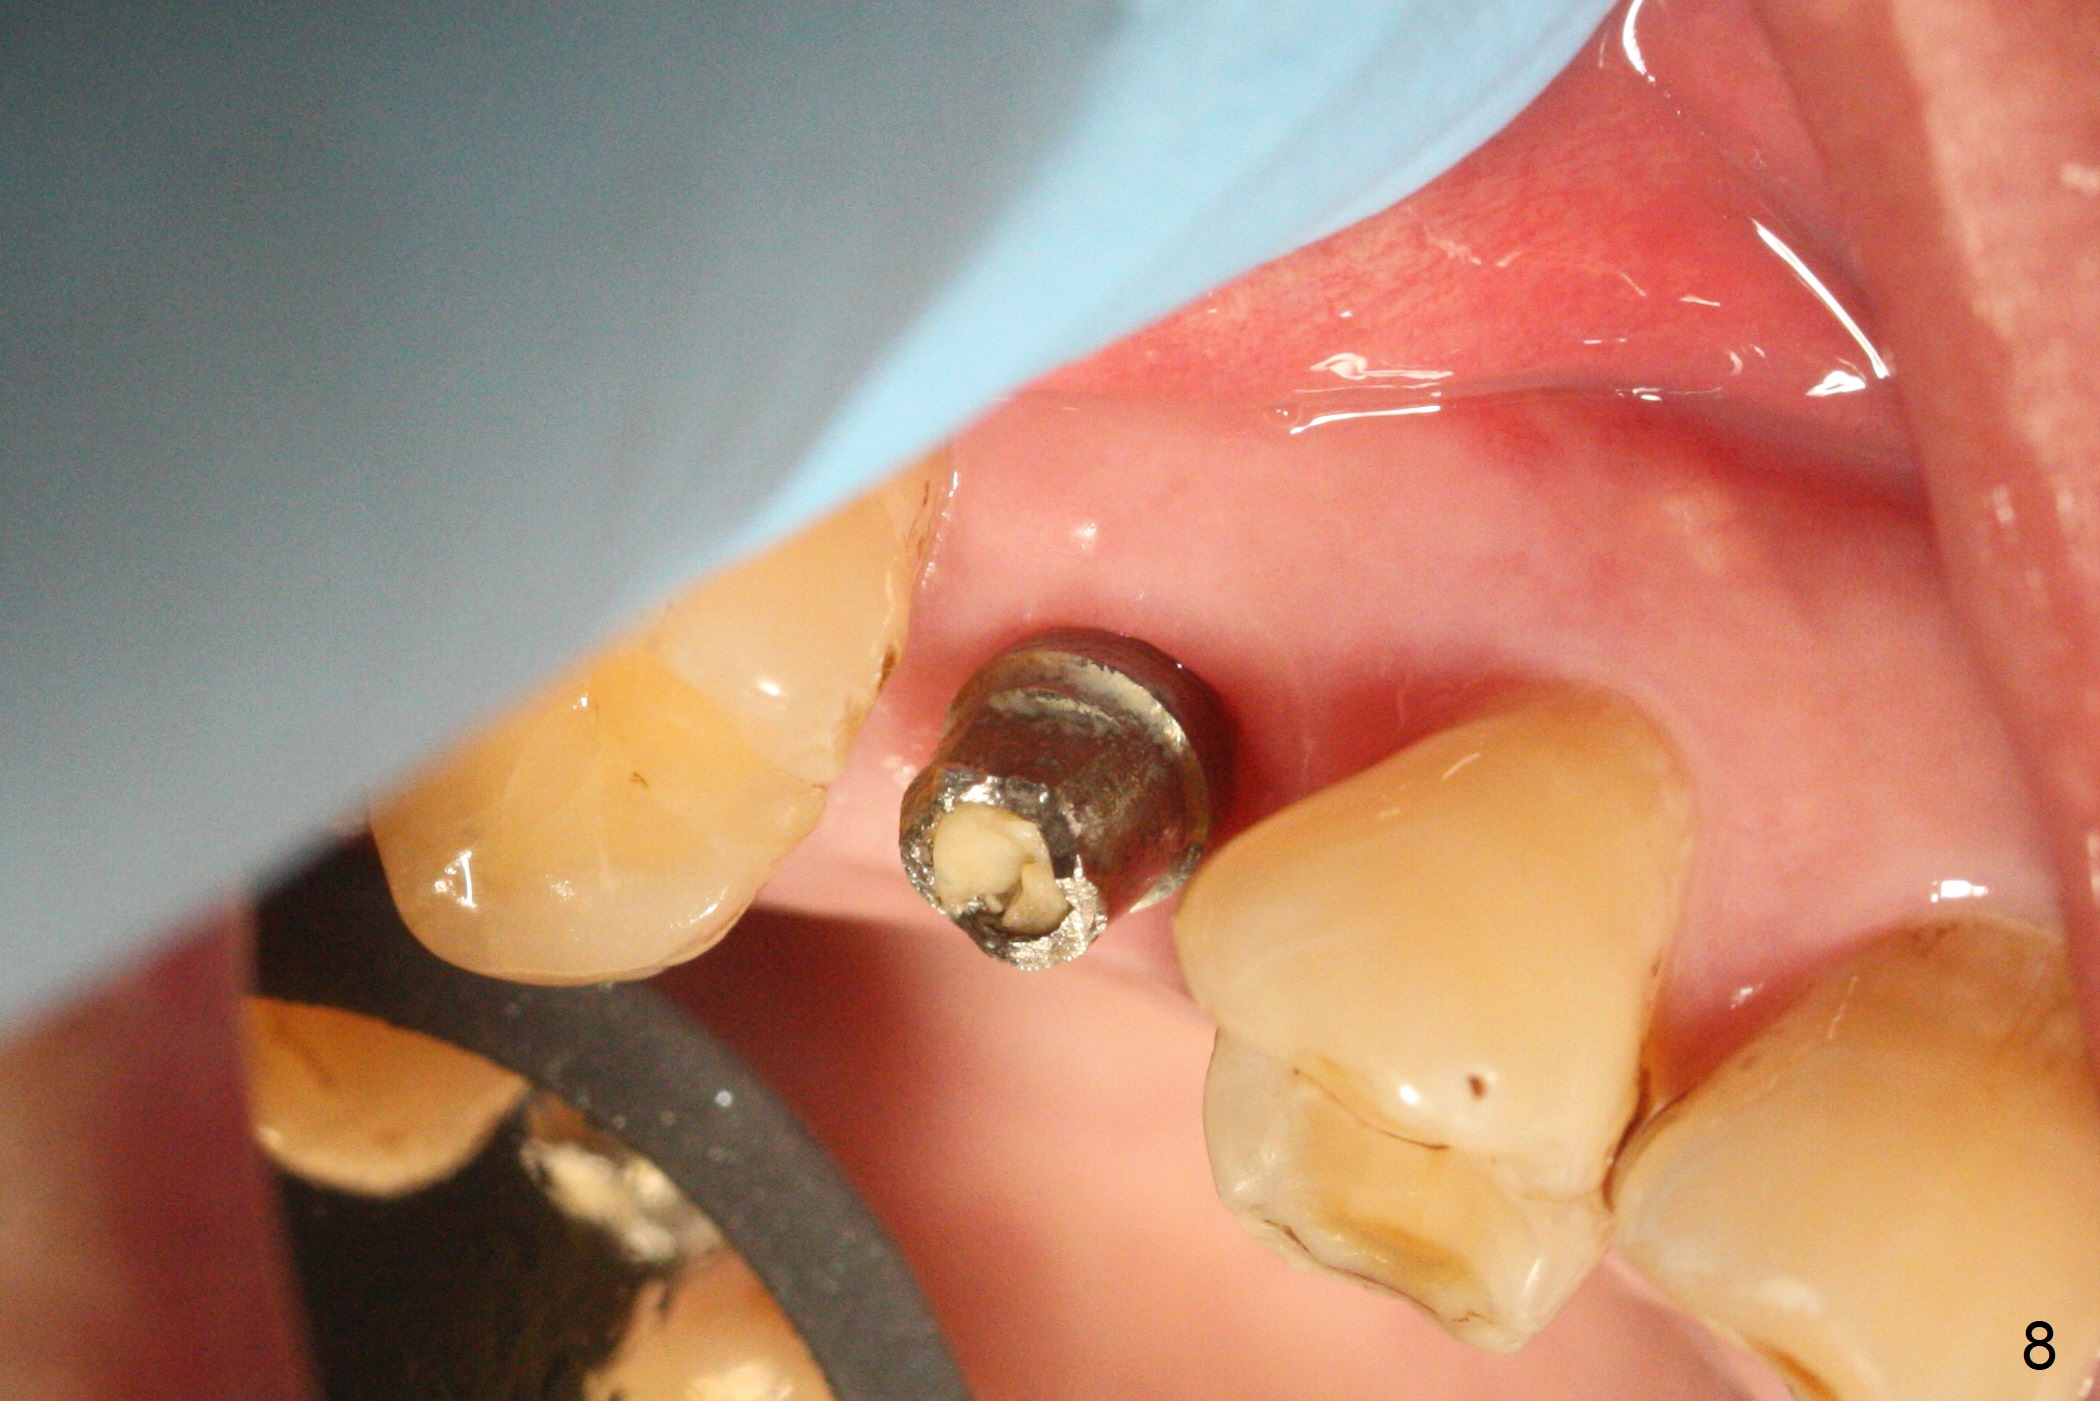

A 47-year-old man returns emergently with subgingival fracture of the lingual (L) cusp of the tooth #4 (Fig.1-3). After extraction (no bony defect) without drilling, a 4x11 mm dummy implant is placed as a tap drill with satisfactory stability (Fig.4,5). To get subcrestal placement, a shorter (4x9 mm) implant is inserted with insertion torque of < 35 Ncm. In retrospect, a larger implant (4.5 mm) would be better in term of primary stability. After allograft placement into the buccal and lingual gaps, a 4.5x4(4) mm abutment is placed for an immediate provisional. There is a peri-implant gap 7 months postop (Fig.7<, as compared to the implant at #2 (6 months postop)) . When the loose abutment is being retightened, the patient feels pain, although the gingiva appears healthy (Fig.8). A larger implant should have been used; the abutment should have been removed. The implant dislodges while the abutment is untightened 8 months postop. The osteotomy is found intact. A 4.5x11 mm dummy implant is placed 2 mm subgingival with 20 Ncm (Fig.9). When a 4.5x11 mm definitive implant is placed 3 mm subgingival (Fig.10,11), torque reaches 50 Ncm. A 5.5x3 mm healing abutment is placed. Three months postop, the implant is stable (Fig.12,13) and impression is taken.